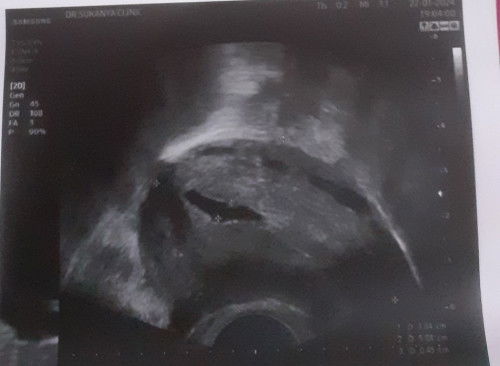

อยากเล่าความเป็นเเม่มือใหม่เเละความโง่ตัวเองค่ะ กำหนดคลอด10ตุลาคม63 เเต่คลอดน้องก่อนกำหนด34วีคพอดีค่ะ ตอนได้น้องตอนนั้น32วีคกว่าๆ ตื้นเช้ามาน้ำคร่ำเเตกจ้า ด้วยความไม่รู้ว่าน้ำคร่ำเเตก เพราะไม่มีอาการเจ็บท้องใดๆ ไม่มีมูกเลือด มันเหมือนเยี่ยวธรรมดาไหลมา เลยไม่ได้สงสัย จนเช้าของอีกวัน บอกเเฟนว่า มีน้ำใสๆไหลออกมา เเฟนเเละเเม่ก็พาไปโรงบาลทันที ไปถึงปั้บ หมอให้เเอดมินดูอาการ1อาทิตย์ หมอบอก ไม่ให้ลุกเดินบ่อย คือต้องนอนอยู่กับที่ตลอดเวลา ลุกได้เฉพาะญาติมาเยี่ยม น้ำคร่ำก็ยังไหลเรื่อยๆตลอดเวลา ตลอดที่เเอดมิน1อาทิต ฉีดยากระตุ้นปอดเด็ก ตอนจะได้กลับบ้าน หมอซาวด์ดู น้ำคร่ำเหลือน้อย กลัวสายสะดื้อพันคอน้อง เเต่หมอบอกว่า น้องเเข็มเเรงมาก ดิ้นเก่งมาก เเล้วหมอนัดตรวจน้ำคร่ำอีกที3วัน พอกลับบ้านปั้บ น้ำก็ยังไหลเรื่อยๆ ไม่มีท่าทีที่จะเจ็บท้อง ไม่มีอาการอะไร เเต่น้ำก็ยังไหลเหมือนเยี่ยวตลอดเวลา พอถึงวันนัด หมอตรวจน้ำคร่ำ น้ำคร่ำก็เหลือน้อย เเล้วหมอก็ให้เเอดมินน้องรอดูอาการเหมือนเดิม นอนรอจนเเม่ๆคนอื่น เขามาคลอด จนได้ไปพักห้องฟื้นหมดเเล้ว เรายังไม่มีอาการที่จะเจ็บท้องเลยค่ะ พอครรภ์ครบ34วีคพอดี หมอเจาะน้ำคร่ำให้ค่ะ เเล้วก็ยังไม่มีอาการเจ็บท้อง ใดๆ เช้าของอีกวัน หมอมาใส่ยาเร่งคลอดให้น้องคลอดค่ะ เร่งคลอดให้ตอนนเช้า เเต่ก็ยังไม่มีอาการใดๆ ไม่มีเจ็บท้องเลยค่ะ หมอก็ดูอาการเรื่อยๆ จนเช้าของอีกวัน หมอใส่ยาเร่งคลอดให้ค่ะ จนเที่ยงเเล้วก็ยังไม่มีอาการใดๆเลยค่ะ พอช่วง6โมงเย็น เริ่มมีอาการเจ็บท้องถี่ๆขึ้นมา เจ็บพอทนได้ พอเริ่มประมาณ 2-3ทุ่มขึ้นไป ทรมานค่ะอยู่ไม่ได้ ร้องลั่นห้องเลยจ้า เจ็บมาก เจ็บเเบบเจ็บลงไปในล่องก้น เจ็บเเบบอธิบายไม่ถูกอะค่ะ คือเเบบจะเเบ่งอย่างเดียว พอหมอมาตรวจปากมดลูก ปากมดลูกก็เปิดได้เเค่5เซ็น คือไม่ไหวเเล้วค่ะ หมอมาตรวจอีกได้7เซน หมอบอกอย่าพึ่งเเบ่งนะคะ คือเราทนไม่ไหวคะ เราเเอบเเบ่งเอง เเบ่งจนหัวน้องจะออกเเล้ว พยายามรีบมาดูค่ะ เเบ่ง3ที น้องออกมาค่ะ น้องเป็นผช.น้ำหนัก2180กรัมเองค่ะ น้องเเข็งเเรงดีค่ะ เเต่หมอบอกว่า น้องหายใจเร็ว เลยได้อยู่ตู้อบ1วันค่ะ พอมาพักห้องฟื้น คือน้ำนมเราไหลค่ะ ไหลเยอะมาก ไหลอาบเเบบน้ำอาบเลยค่ะ มันไหลออกมาเองเยอะมาก คัดนมมาก เพราะลูกไม่ได้กินนม พอวันที่2หมอเอาลูกมาให้ เอามาให้เข้าเต้า เเอบน้อยใจค่ะ น้ำนมเยอะมาก นั่งเฉยๆ น้ำนมนี้ไหลเปียกเสื้อหมด เเต่น้อยใจตรงทีว่า เอาน้องเข้าเต้าเเล้ว น้องไม่ยอมดูเต้าค่ะ ทำยังไงก็ไม่ยอมดู จนพยาบาล มาช่วงเอาน้องเข้าเต้า ทำยังไงน้องก็ไม่ดูค่ะ น้องดิ้น น้องหันหน้าหนี้ จนหมอสุดความสามารถเเล้วค่ะ สุดท้าย ได้ป้อนนมกระป๋องคุณหมอจากสหริ่ง เเละซื้อขวด ปั้มนมให้กินเอาจ้า น้องงได้อยู่โรงบาล1อาทิต เพราะน้องตัวเหลือง #น้ำหนักน้องเเรกคลอด2,180 กรัม #ออกจากโรงบาล2,200กรัม #ขอบคุณที่เข้ามาอ่านค่ะ #ตอนนี้น้องได้8เดือน 12โลกว่าเเล้วค่ะ